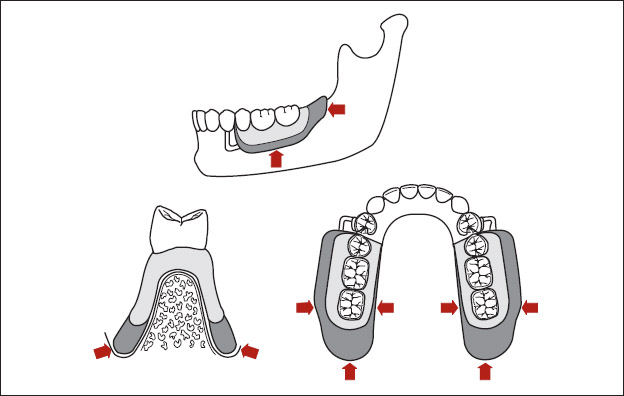

Kennedy Class I removable partial dentures present significant challenges for patients and dentists alike. Because Class I removable partial dentures exhibit bilateral extension bases, they must derive support from the remaining teeth and residual ridges (Fig 1-36). To preserve the remaining teeth and residual ridges, removable partial dentures must provide an equitable distribution of forces. Concentration of forces upon the remaining teeth may produce rapid destruction of the periodontal tissues and potential abutment loss. Concentration of forces upon the residual ridges may produce rapid destruction of the associated tissues and an accompanying decrease in ridge height. Consequently, practitioners must carefully consider the effects of removable partial denture design upon the remaining oral structures. The following features must be included in the design of Class I removable partial dentures: provision of optimum support for the distal extension denture bases, incorporation of flexible direct retention, and provision of indirect retention.

Fig 1-36 A Kennedy Class I removable partial denture must derive support from the teeth and soft tissues.

All portions of a residual ridge that are capable of providing support should be covered by an accurately fitting denture base. Broad coverage permits a favorable distribution of stresses, often described as a snowshoe effect (Fig 1-37). Inadequate soft tissue coverage can lead to stress concentration, breakdown of underlying bone, and a decrease in ridge volume. Adequate support of a distal extension base is often so critical that a second impression of the residual ridge is required. The technique and rationale for this procedure are covered in chapter 13.

Fig 1-37 Full extension of the denture base permits a more favorable distribution of applied forces. The lightly shaded area depicts an underextended denture base. The darker shading depicts a denture base that has been fully extended.

The soft tissues are displaceable and allow vertical movement of the denture bases upon loading (Fig 1-38). Vertical displacement of the denture bases may result in the application of stresses to the most posterior abutments. Improperly designed direct retainers may magnify these stresses. The resultant “rocking” forces may damage the associated periodontal tissues and produce mobility of the abutment teeth. Therefore, direct retainers must permit dissipation of forces resulting from denture base movement. Each direct retainer should be designed to flex or move into an area of greater undercut as forces are applied to the removable partial denture. Clasp design is a key factor in successful removable partial denture service.

Fig 1-38 Because the soft tissues are displaceable, loading often produces vertical movement of denture bases. Flexible direct retention must be utilized to prevent the application of harmful torquing forces to the abutments.

In some instances, sticky foods may lift denture bases away from the supporting tissues. This displacement produces rotation of the removable partial denture around the most posterior abutment (Fig 1-39). Rotation must be controlled to prevent damage to the remaining teeth and oral tissues. To accomplish this objective, auxiliary rests should be placed as far as practical from the fulcrum line. Because the auxiliary rests minimize rotation and aid in retention of the associated prosthesis, they are termed indirect retainers. The concept of indirect retention is discussed in detail in chapter 3.

Fig 1-39 Indirect retention must be provided in Class I applications. (a) An extension base removable partial denture that lacks appropriate indirect retention (arrow). (b) When the denture base moves away from the underlying soft tissues (large arrow), uncontrolled rotation of the removable partial denture occurs (small arrows). (c) Indirect retention has been provided (arrow). (d) When an unseating force is applied to the denture base (arrow), the indirect retainer resists rotation.